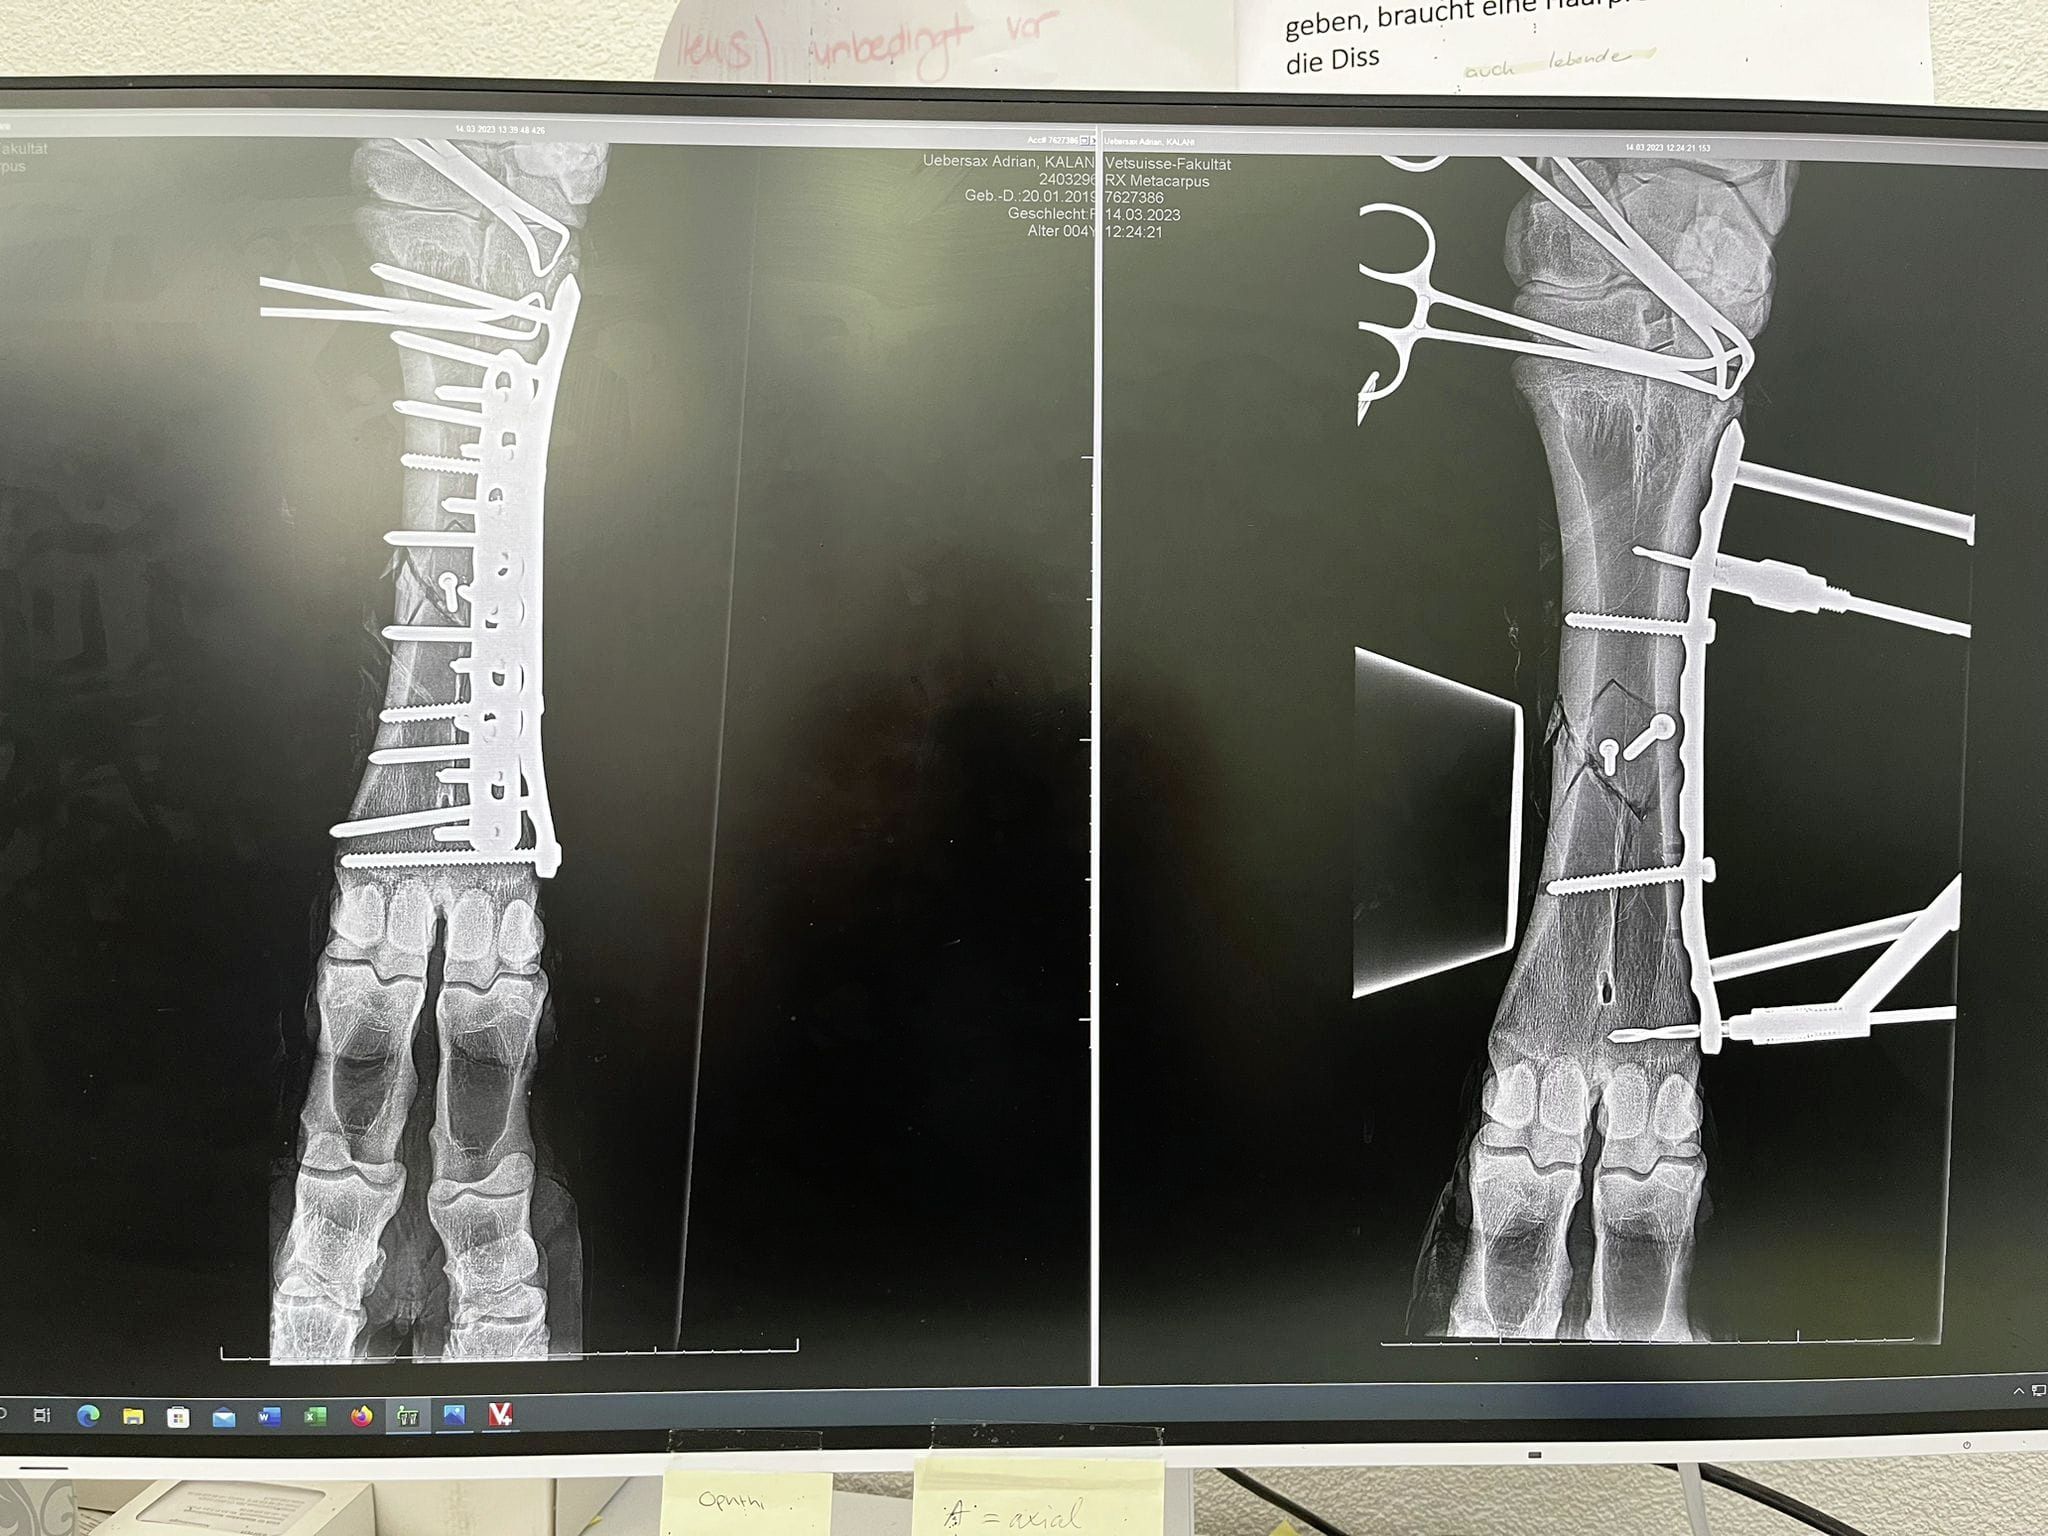

Das Bein wurde samt Gips geröntgt, man hat gesehen, dass sich der Bruch nicht verschoben hat. Der Bruch war an einer Stelle, an der eine Operation mit grossen Erfolgsaussichten theoretisch möglich war. Für Kalani gab es drei Behandlungsmöglichkeiten. Erstens: Keine Operation und das Bein nur mit Gips fixieren und stabilisieren. Zweitens: Eine Operation mit leichter Fixierung der Bruchstelle mit Schrauben und Gips. Drittens: Eine Operation mit Fixierung der Bruchstelle mit Platten und Schrauben und einem Gips.

Ich habe gesagt, wenn schon, dann die Möglichkeit mit der grössten Erfolgsaussicht und das war die Dritte. Kalani wurde am nächsten Morgen noch einmal ohne Gips geröntgt, die Ausgangslage und Erfolgschancen waren so gut, dass anschliessend in einer 5,5-stündigen Operation der Bruch fixiert wurde.